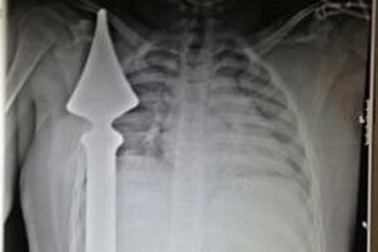

Thoát chết thần kỳ khi bị cọc sắt đâm gần timMột cậu bé 12 tuổi đã sống sót thần kỳ sau khi bị ngã vào hàng rào kim loại khiến những cọc nhọn trên hàng rào đâm xuyên qua người và chỉ cách tim của cậu bé vài cm.